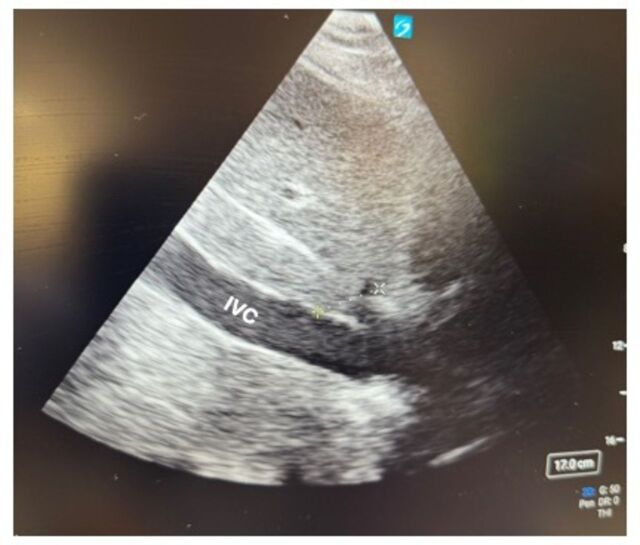

有效的侵入性和非侵入性监测,加上良好的临床决策,可以改善危重患者的预后。在决定最佳监测技术时,重要的是要考虑指导重症监护管理所需的具体信息,同时平衡所获得数据的可靠性和有创监护仪放置的风险。在这里,我们回顾了外科重症监护病房中血液动力学和神经系统监测的侵入性和非侵入性选择。了解每个监测设备的功能、适应症、风险和局限性是决定如何监测指导临床决策的床边生理数据的关键。证据等级:四级。

Effective invasive and non-invasive monitoring, when coupled with good clinical decision making, can improve outcomes for critically ill patients. When deciding on the best monitoring technique, it is important to consider the specific information that is needed to guide critical care management, while balancing the reliability of the data obtained and the risks of invasive monitor placement. Here, we review invasive and non-invasive options for hemodynamic and neurologic monitoring in the Surgical Intensive Care Unit. Understanding how each monitoring device functions, its indications, risks, and limitations is key when deciding how to monitor bedside physiologic data that guide clinical decision making. Level of evidence: Level IV.